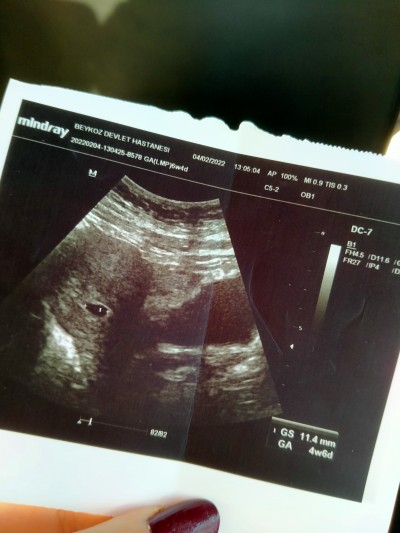

Kizlar benim son regl tarihime gore 6+6 haftalik hamileyim fakat 2. gittigim doktorum gwc dollenme olabilecegini kalp atisi icin biraz daha beklememiz gerektigini soyledi5 hafta 4 gun dedi.1 hafta geriden gidiyorum bu doktorun dedigine gore.boyle bir durumu yasayan var mi rahmim hafif kalp seklinde sorun olmayacagini soyledi ayrixa

benim kese boyutum1.35 cm sizin

1.42 cm benimde her şey yolunda ama kalp atışını duymadan içim rahat etmeyecek sanırım bekliyorum hayırlısı ile duyarız inşallah